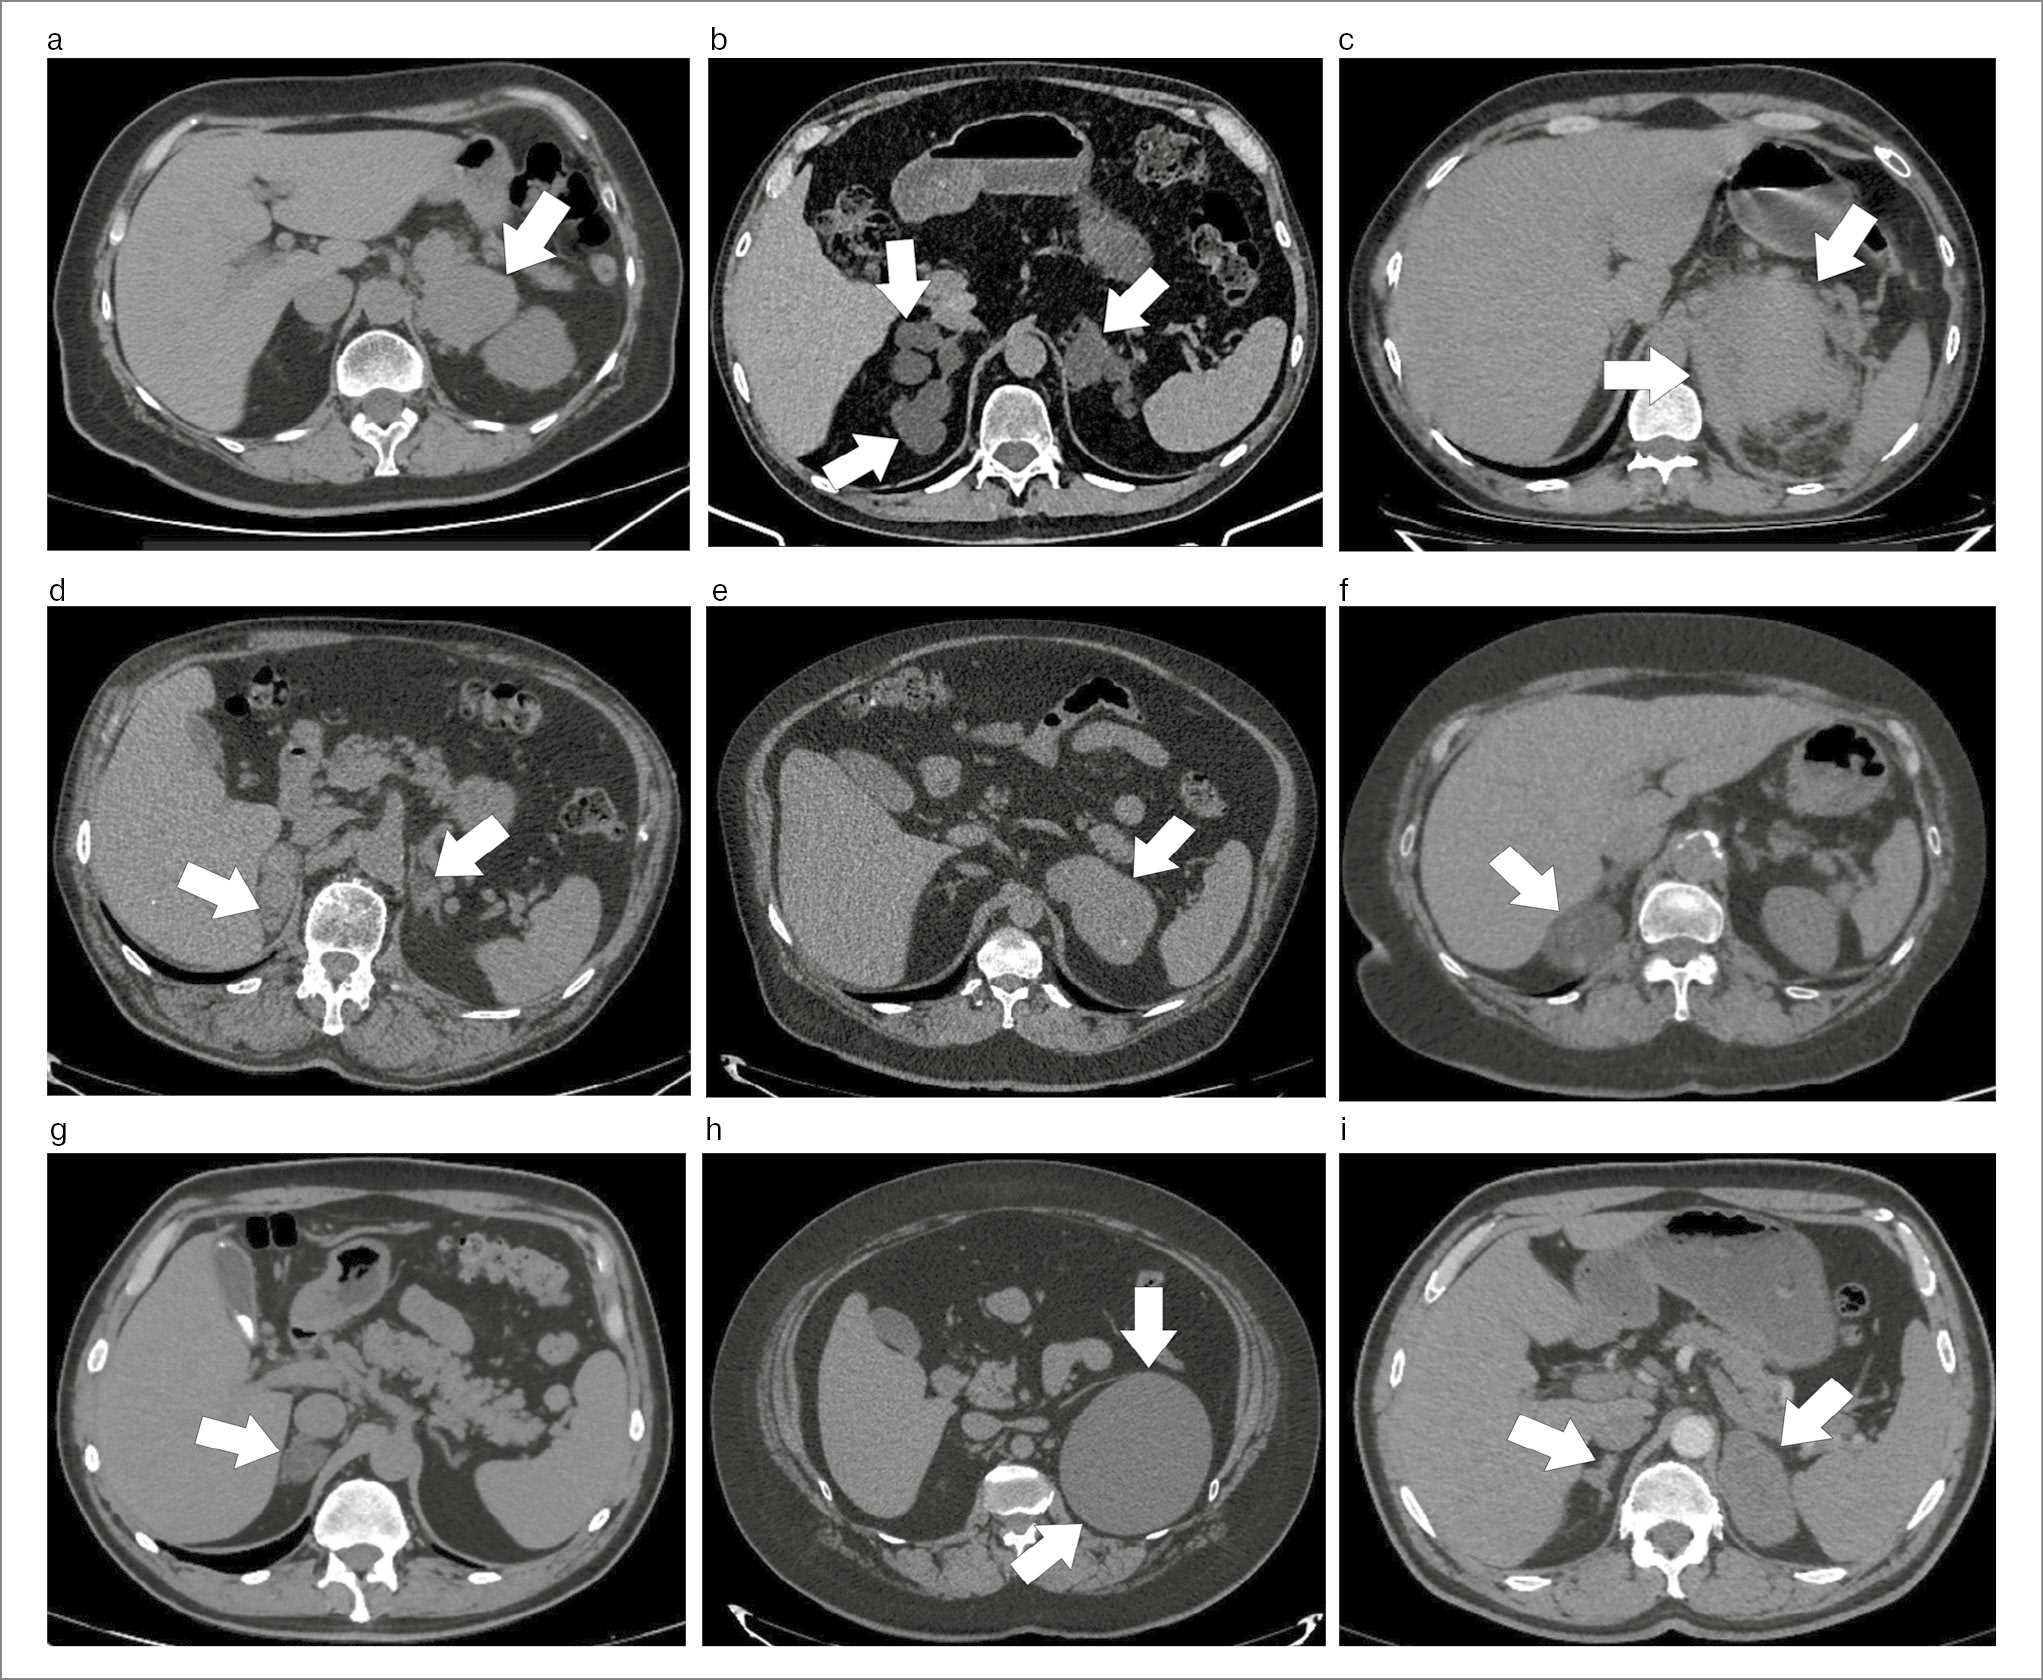

Рис. 1. КТ-изображения инциденталом надпочечников: a – феохромоцитома левого надпочечника размером 69×57×45 мм высокой нативной плотности (25–35 HU); b –двусторонняя макронодулярная гиперплазия надпочечников: правый надпочечник от 14 до 26 мм, с точечными кальцинатами в наиболее крупном из образований. Левый надпочечник – от 10 до 52 мм; плотность – 0–10 HU; c – лимфома левого надпочечника размером 80×64×53 мм с без четких контуров, высокой нативной плотности (от 40–50 HU); d – двусторонние метастазы светлоклеточного рака почки в надпочечники. В правом надпочечнике образования овальной формы, с четкими и ровными контурами, максимальным размером 36×29×32 мм, плотностью от 23–48 HU (при комбинированной позитронно-эмиссионной и рентгеновской КТ SUV 4). В левом надпочечнике образование округлой формы, с четкими и ровными контурами, размерами 21×20×25 мм, плотностью от 29 HU (при комбинированной позитронно-эмиссионной и рентгеновской КТ SUV 3,2); e – АКР левого надпочечника с неровными контурами, вытянутой овальной формы, размерами 48×91×61 мм, плотностью до 35 HU; f – миелолипома правого надпочечника с четкими, ровными контурами размером 49×34×41 мм, плотностью 30 HU; g – аденома (альдостерома) правого надпочечника с ровными четкими контурами, размерами 22,5×18,3×28,6 мм, плотностью 10 HU; h – киста левого надпочечника размерами 113×105×115 мм, плотностью во все фазы исследования 20 HU; i – объемные ОН на фоне длительной декомпенсации врожденной дисфункции коры надпочечников. В правом надпочечнике узелки максимальным размером 10×12 мм, плотностью 33 HU. В левом надпочечнике структура с четкими и неровными контурами, максимальным размером 66×34×42 мм, плотностью до 37 HU.

Аденомы надпочечников (рис. 1, g) составляют большинство случайно выявленных ОН (81–88%) [6, 7]. На момент постановки диагноза средний размер аденомы надпочечника составляет 1,5–2,5 см, при этом 95–98% из них имеют размер <4 см [2, 3, 7]. Двусторонние аденомы выявляются примерно у 15% пациентов. При визуализации около 60% аденом богаты жировой тканью и имеют нативную плотность <10 единиц Хаунсфилда (HU), в 25% случаев плотность находится в диапазоне от 10 до 19 HU и в 15% – >20 HU. ФАПК диагностируется у 35–50% пациентов (табл. 1) [1, 2]. Следует отметить, что гормонально активные аденомы зачастую выявляются случайно после проведения радиологических исследований, а не по причине наличия симптомов гиперкортицизма или гиперальдостеронизма [6, 8].

Миелолипомы надпочечников (рис. 1, f) диагностируются у 3,3–6,2% пациентов с инциденталомами (см. табл. 1). Средний размер миелолипом от 2 до 2,5 см; однако он может значительно варьировать от 0,5 до 15 см и более. Двусторонние миелолипомы встречаются у 5% от общего количества миелолипом и в 20% случаев – среди инциденталом размером >6 см [9].

Доброкачественные некортикальные ОН, отличные от миелолипом, встречаются редко, составляя в общей сложности 1–2%, и включают ганглионевромы, кисты (рис. 1, h), гемангиомы, лимфомы (рис. 1, c) и шванномы [2, 6, 7]. КТ- и МРТ-семиотика этих образований не специфична, диагноз часто ставится на основании гистологического исследования после проведения адреналэктомии.

Имеющие клинические проявления феохромоцитомы представляют собой крупные опухоли со средним размером от 4 до 5 см, которые в 4–10% случаев имеют двустороннюю локализацию [10]. Подавляющее количество феохромоцитом при проведении КТ (рис. 1, a) имеет плотность >20 HU (92%), при этом только у 7,5% плотность образования находится в диапазоне от 10 до 20 HU, а у 0,5% пациентов равна 10 HU.

АКР

АКР (рис. 1, e) является редким злокачественным ОН и составляет примерно 0,3% всех ОН и 3,6% злокачественных ОН в популяционной выборке [2]. В то же время AКР является наиболее часто диагностируемым злокачественным ОН в эндокринологической клинике и выявляется примерно у 5% пациентов, наблюдаемых эндокринологом (см. табл. 1) [7]. АКР обнаруживается случайно при проведении визуализирующих обследований по другим причинам в 42–44% случаев [7, 8], несмотря на то, что при обследовании эти образования оказываются гормонально активными. АКР представляет собой одностороннее образование, при этом большинство карцином на момент обнаружения имеют средний размер 10 см [7, 8]. При визуализации карциномы являются либо гетерогенными опухолями, либо имеют плотность >20 HU по данным КТ, медиана плотности составляет 35 HU [7, 8]. Только 2% АКР обнаруживаются при размере опухоли <4 см, и только у 1% плотность составляет от 10 до 20 HU [7].

Метастазы в надпочечниках или другие злокачественные образования

Метастазы (рис. 1, d) являются наиболее распространенным злокачественным ОН, на долю которых приходится 7,5% всех ОН и 86% всех злокачественных новообразований надпочечников в популяции [2]. Однако метастазы в надпочечники гораздо реже встречаются в практике эндокринолога, и только 1 из 4 пациентов с метастазами в надпочечники проводится исключение гормональной активности выявленного образования [2, 12, 13]. Несмотря на то что большинство метастазов в надпочечники обнаруживаются при проведении динамического наблюдения за пациентами с онкологическими заболеваниями, 36% выявляются случайно [12]. Средний размер образований составляет 3 см, варьируя от 0,5 до 20 см (см. табл. 1) [12]. Нередко встречается двустороннее метастазирование в надпочечники [12]. У 12% пациентов с двусторонними метастазами в надпочечники диагностируется первичная надпочечниковая недостаточность [12]. Редко встречающимися злокачественными ОН являются лимфомы, саркомы и нейробластомы [2, 7, 8].

По данным физикального обследования ИМТ – 23,6 кг/м2, артериальное давление – 115/64 мм рт. ст. Выполнено повторное КТ, по результатам которого определяется образование левого надпочечника размером 6,8 см, нативной плотностью HU 36 (см. рис. 1, e). В сравнении с предыдущим исследованием отмечен рост образования на 1 см. Результаты лабораторных анализов представлены в табл. 3.

По поводу выявленных двусторонних ОН обратилась 47-летняя женщина. За последние 3 года отмечает постепенное увеличение массы тела на 12 кг, появление надключичных жировых «подушечек» и климактерического горбика, стрий на внутренней поверхности бедер и животе, беспокойство и бессонницу. Кроме того, 8 мес назад у нее диагностировали артериальную гипертензию и СД 2 (HbA1c 7,8%). На момент обследования пациентка получала следующую терапию: лизиноприл, амлодипин, гидрохлоротиазид и метформин. При физикальном осмотре: артериальное давление 163/97 мм рт. ст., ИМТ – 31,7 кг/м2, стрии на животе и внутренней поверхности бедер, лунообразное лицо, матронизм, дорсоцервикальные и надключичные жировые «подушечки». Заподозрен СК, проведены соответствующие лабораторные анализы (см. табл. 3). При повторной оценке результатов КТ выявлены двусторонние ОН 1,4×2,6 см справа и 1,0×5,2 см слева, сходной нативной плотности 5 HU (рис. 1, b).